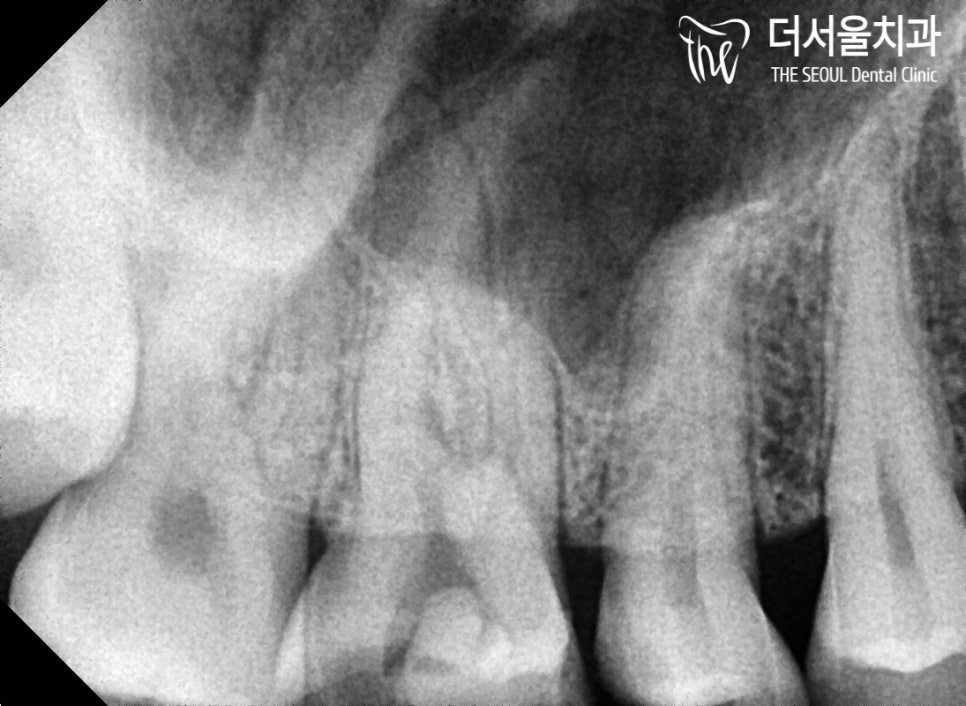

코어 작업까지 마치고

이제 최종 보철을 올려드릴 차례죠?

환자께서 마음에 쏙! 들어하실

지르코니아를 사용하여

크라운을 제작했습니다.

성남치과 에서

교합 조정 및 약간의 외관 수정을 마친 후

최종 부착을 도와드렸습니다.

환자께서도 마음에 쏙 들어하셨는데요.